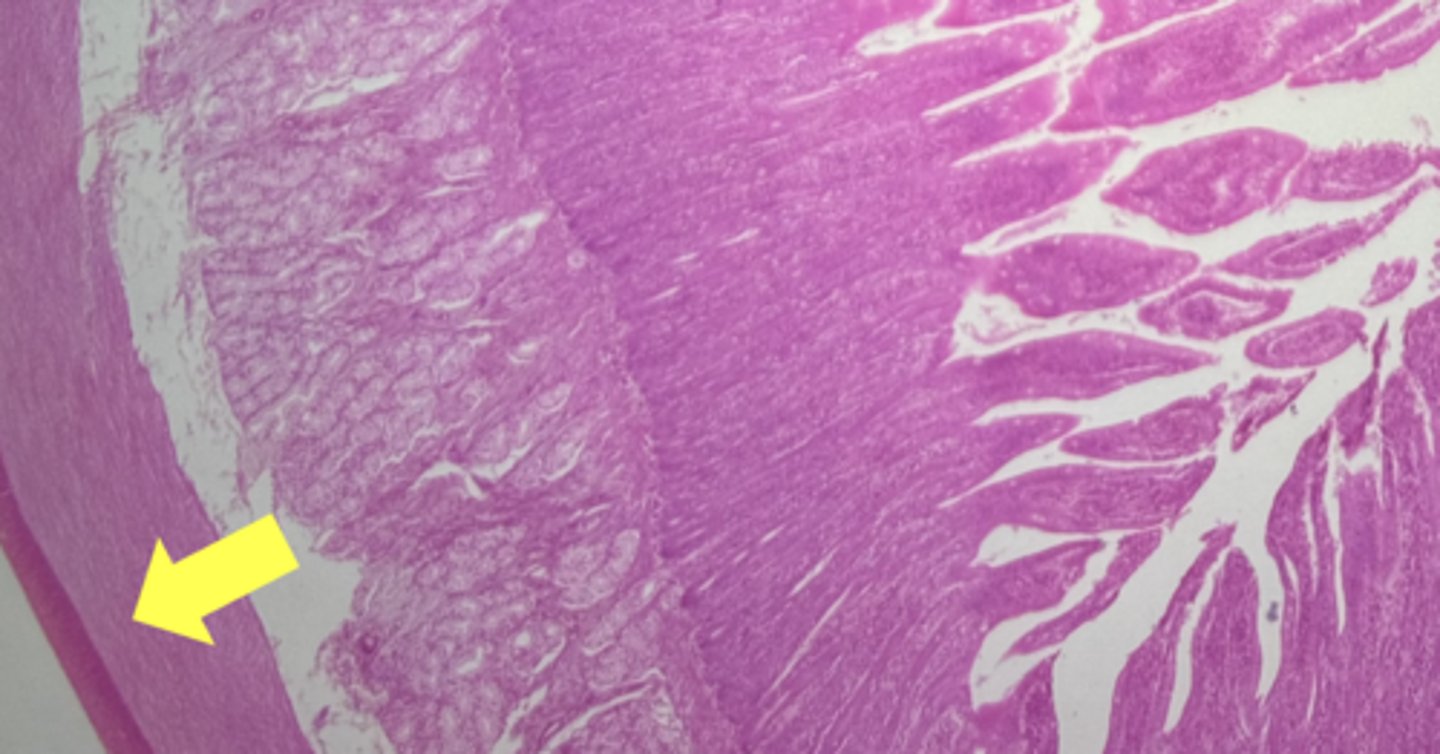

stomach

name the tissue

mucosa

(stomach)

submucosa

muscularis externa (3 LAYERS-KEY CHARACTERISTIC)

oblique layer

circular layer

longitudinal layer

simple columnar epithelium

gastric pits (KEY CHARACTERISTIC)

gastric glands (KEY CHARACTERISTIC)

Lamina propria

muscularis mucosae